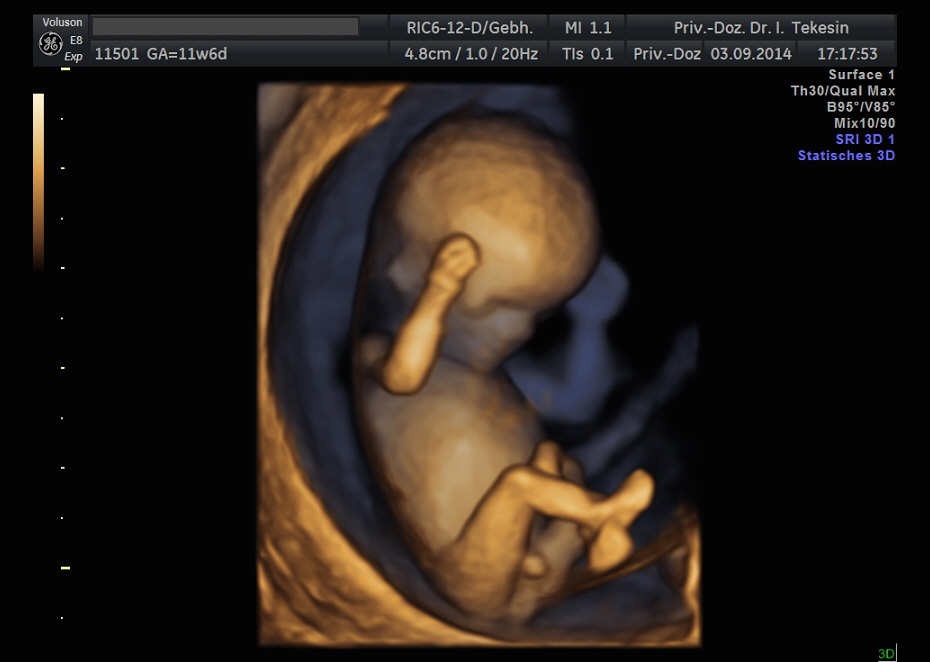

Kind in der 12. Woche (3D-Darstellung)